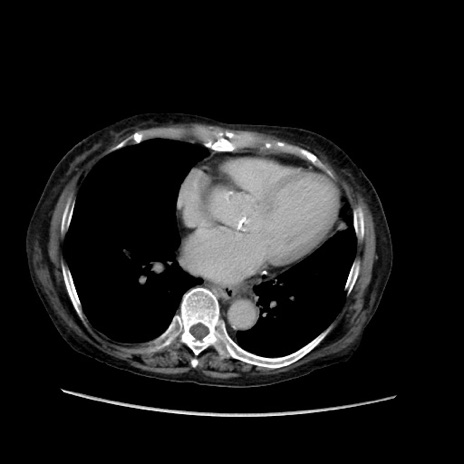

症例31(横断像)

【症例】80歳代 女性

【主訴】腹部膨満感

【現病歴】他院にて肝硬変にてフォロー中。1週間前から便秘、腹部膨満感、臍部腫瘤あり受診となる。

【既往歴】肝硬変

【身体所見】腹部膨隆あり、皮膚変化なし、疼痛なし。

【データ】WBC 4600、CRP 0.25